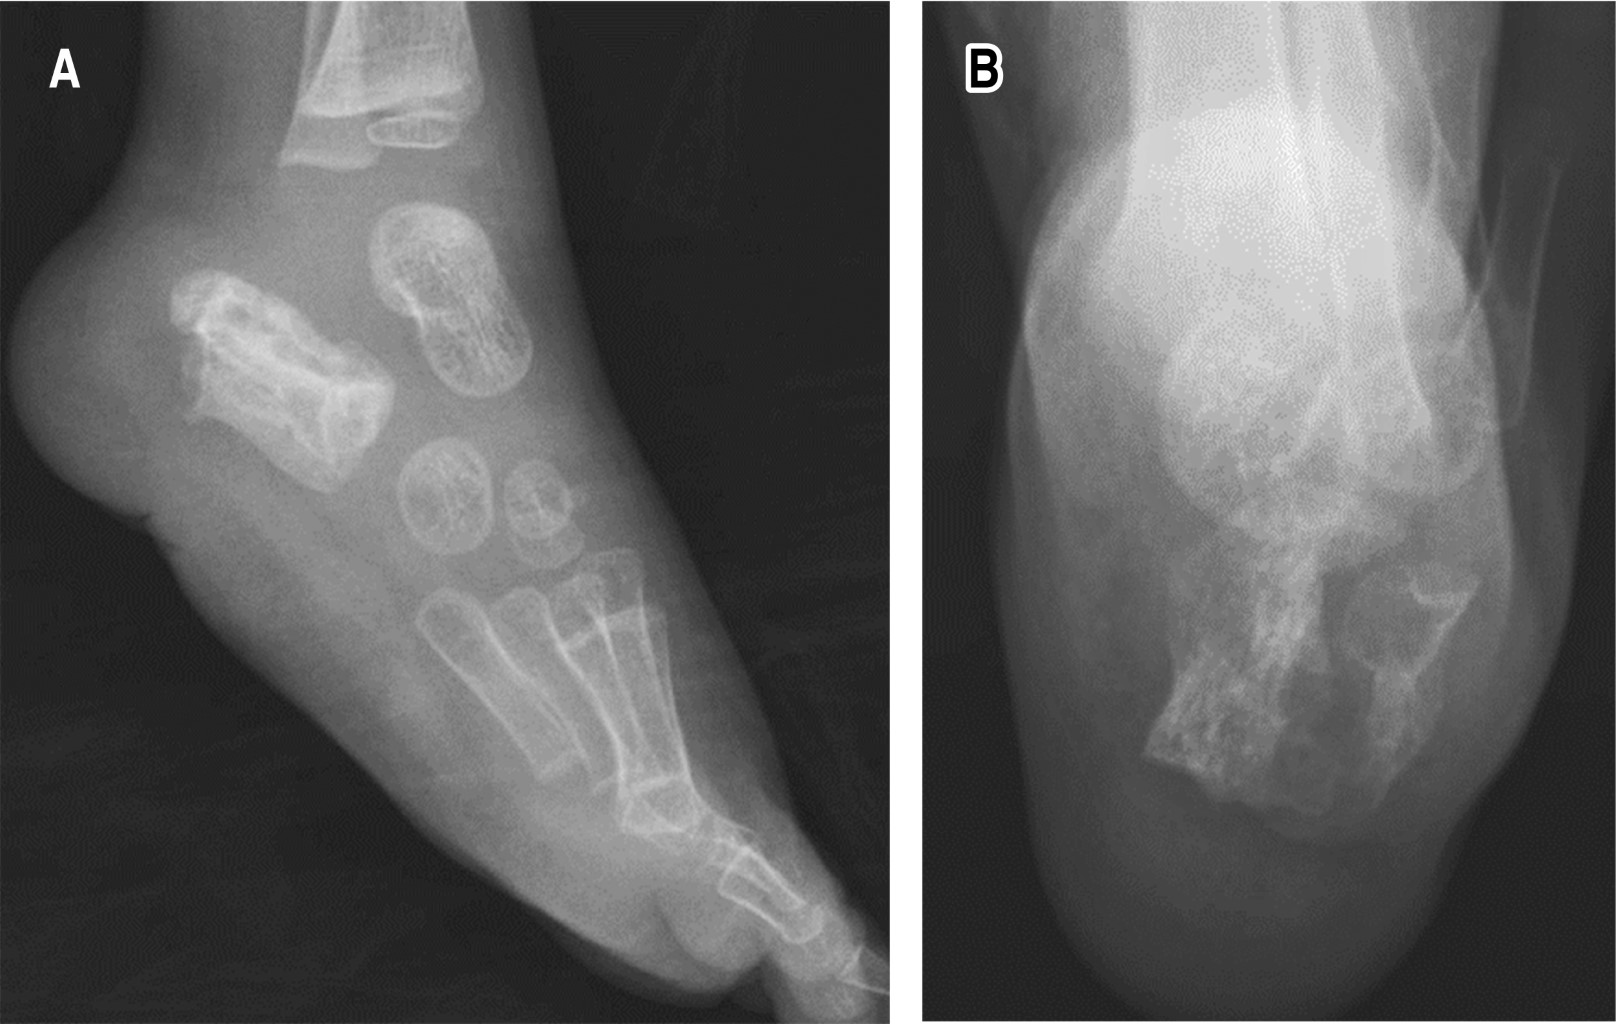

Radiografías anteroposterior (AP) y lateral de tobillo izquierdo. Calcáneo con múltiples imágenes radiolúcidas circulares delimitadas con un halo radiopaco más una pérdida de la radiopacidad en la cortical posteroinferior sustituida por imágenes heterogéneas e irregulares, asociado a radiolucidez marcada de los tejidos blandos (Figura 2).

Radiográficamente, en las proyecciones iniciales de calcáneo, nuestro paciente presentó múltiples imágenes radiolúcidas circulares de diversos tamaños delimitadas por un halo radiopaco, asociado a una pérdida de la radiopacidad en la cortical posteroinferior del calcáneo sustituida por imágenes heterogéneas e irregulares, hallazgos similares a los descritos en la literatura para una afección ósea por M. tuberculosis donde se describen imágenes secundarias a reabsorción trabecular con afección cortical y de tejidos blandos asociada a afección articular. El caso de nuestro paciente contaba con una tomografía axial computarizada en la cual se demuestra la destrucción tanto de hueso trabecular como cortical y la presencia de aire en la porción con pérdida ósea.7